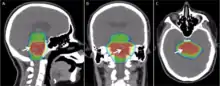

Radiation therapy is commonly applied to the cancerous tumor because of its ability to control cell growth. Ionizing radiation works by damaging the DNA of cancerous tissue leading to cellular death. To spare normal tissues (such as skin or organs which radiation must pass through to treat the tumor), shaped radiation beams are aimed from several angles of exposure to intersect at the tumor, providing a much larger absorbed dose there than in the surrounding healthy tissue. Besides the tumour itself, the radiation fields may also include the draining lymph nodes if they are clinically or radiologically involved with the tumor, or if there is thought to be a risk of subclinical malignant spread. It is necessary to include a margin of normal tissue around the tumor to allow for uncertainties in daily set-up and internal tumor motion. These uncertainties can be caused by internal movement (for example, respiration and bladder filling) and movement of external skin marks relative to the tumor position.

Delivery parameters of a prescribed dose are determined during treatment planning (part of dosimetry). Treatment planning is generally performed on dedicated computers using specialized treatment planning software. Depending on the radiation delivery method, several angles or sources may be used to sum to the total necessary dose. The planner will try to design a plan that delivers a uniform prescription dose to the tumor and minimizes dose to surrounding healthy tissues.

An enhancement of virtual simulation is 3-dimensional conformal radiation therapy (3DCRT), in which the profile of each radiation beam is shaped to fit the profile of the target from a beam's eye view (BEV) using a multileaf collimator (MLC) and a variable number of beams. When the treatment volume conforms to the shape of the tumor, the relative toxicity of radiation to the surrounding normal tissues is reduced, allowing a higher dose of radiation to be delivered to the tumor than conventional techniques would allow.[5]

Intensity-modulated radiation therapy (IMRT) is an advanced type of high-precision radiation that is the next generation of 3DCRT.[60] IMRT also improves the ability to conform the treatment volume to concave tumor shapes,[5] for example when the tumor is wrapped around a vulnerable structure such as the spinal cord or a major organ or blood vessel.[61] Computer-controlled x-ray accelerators distribute precise radiation doses to malignant tumors or specific areas within the tumor. The pattern of radiation delivery is determined using highly tailored computing applications to perform optimization and treatment simulation (Treatment Planning). The radiation dose is consistent with the 3-D shape of the tumor by controlling, or modulating, the radiation beam's intensity. The radiation dose intensity is elevated near the gross tumor volume while radiation among the neighboring normal tissues is decreased or avoided completely. This results in better tumor targeting, lessened side effects, and improved treatment outcomes than even 3DCRT.